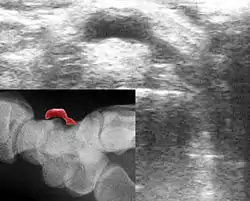

Гангліон зазвичай може бути діагностований за його місцезнаходженням, або формою. Шкіра може бути зміщена, є зв’язок із суглобовою капсулою, або сухожильними піхвами. Однак, оскільки і інші зміни також можуть викликати подібну картину, потрібно зробити підтвердження діагнозу. Це здійснюється за допомогою:

- сонографії суглобу (УЗД)

- рентгенівського знімку ( для диференційної діагностики, бо на звичайному рентген. знімку ганглій не видно).